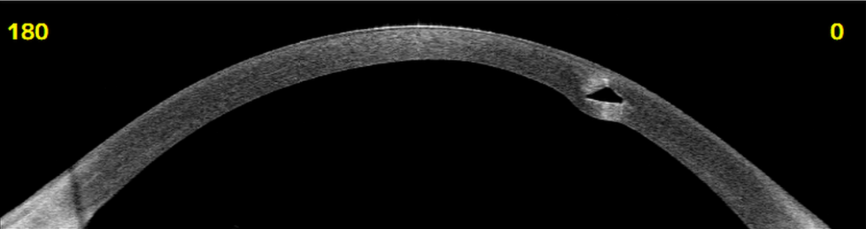

Deze vormverandering kan zich ook op de achterzijde van het hoornvlies bevinden. Gelukkig zijn er uitstekende meetinstrumenten beschikbaar om deze veranderingen te detecteren. Keratoconus leidt tot een verdunning van het hoornvlies, waardoor het essentieel is om regelmatig de dikte van het hoornvlies te meten. Dit kan gebeuren met ultrasone metingen via een pachymeter of nog beter, met een voorsegmentoogscan. Regelmatige controle helpt bij het tijdig herkennen van veranderingen in de ooggezondheid.

De hoornvliesverdunning kan verschillende stadia doormaken, en naast contactlenzen zijn er ook operatieve behandelmogelijkheden. Een veelgebruikte methode is het plaatsen van zogenaamde intacts, waarbij ringen in de cornea worden geïmplanteerd.